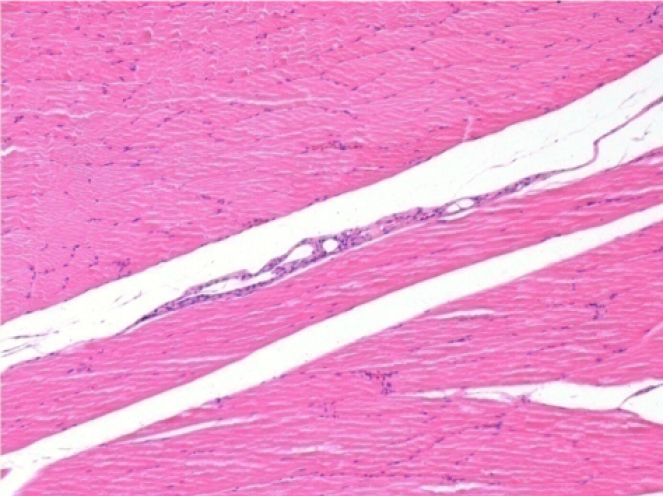

3 meses después de la inyección de Endopeel

3 meses (D90) después de la inyección de Endopeel 0.1ml en el músculo pretibial derecho.

L : Control-100xD90

R:100xD90